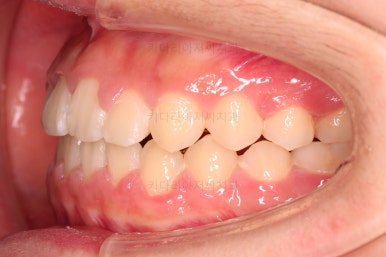

전후 사진을 비교해 볼게요.

악궁확장을 통해 위아래 악궁의 크기 조화를 맞췄고, 틈새도 모았으며 교합도 적절히 마무리를 했습니다.

향후 유지관리가 다른 분들보다 훨씬 중요한 상황이라 볼 수 있겠습니다.